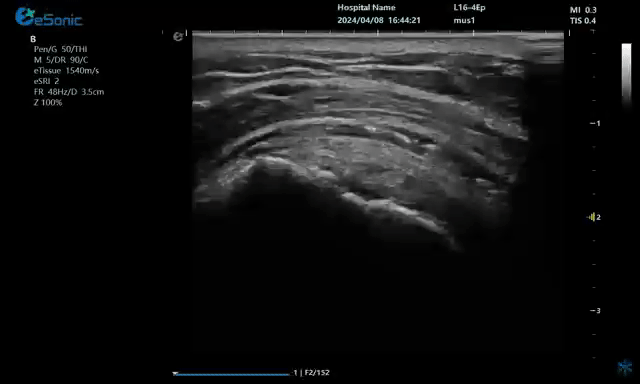

病例:冈上肌肌腱钙化穿刺治疗

640 (2).gif

无磁导航技术引导穿刺钙化点

钙化物.jpg

取出的钙化物